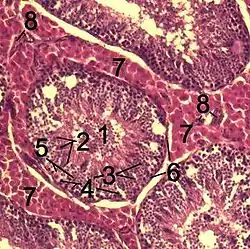

![]() Histological section through testicular parenchyma of a boar. 1. lumen of Tubulus seminiferus contortus 2. spermatids 3. spermatocytes 4. spermatogonia 5. Sertoli cell 6. myofibroblasts 7. Leydig cells 8. capillaries | |